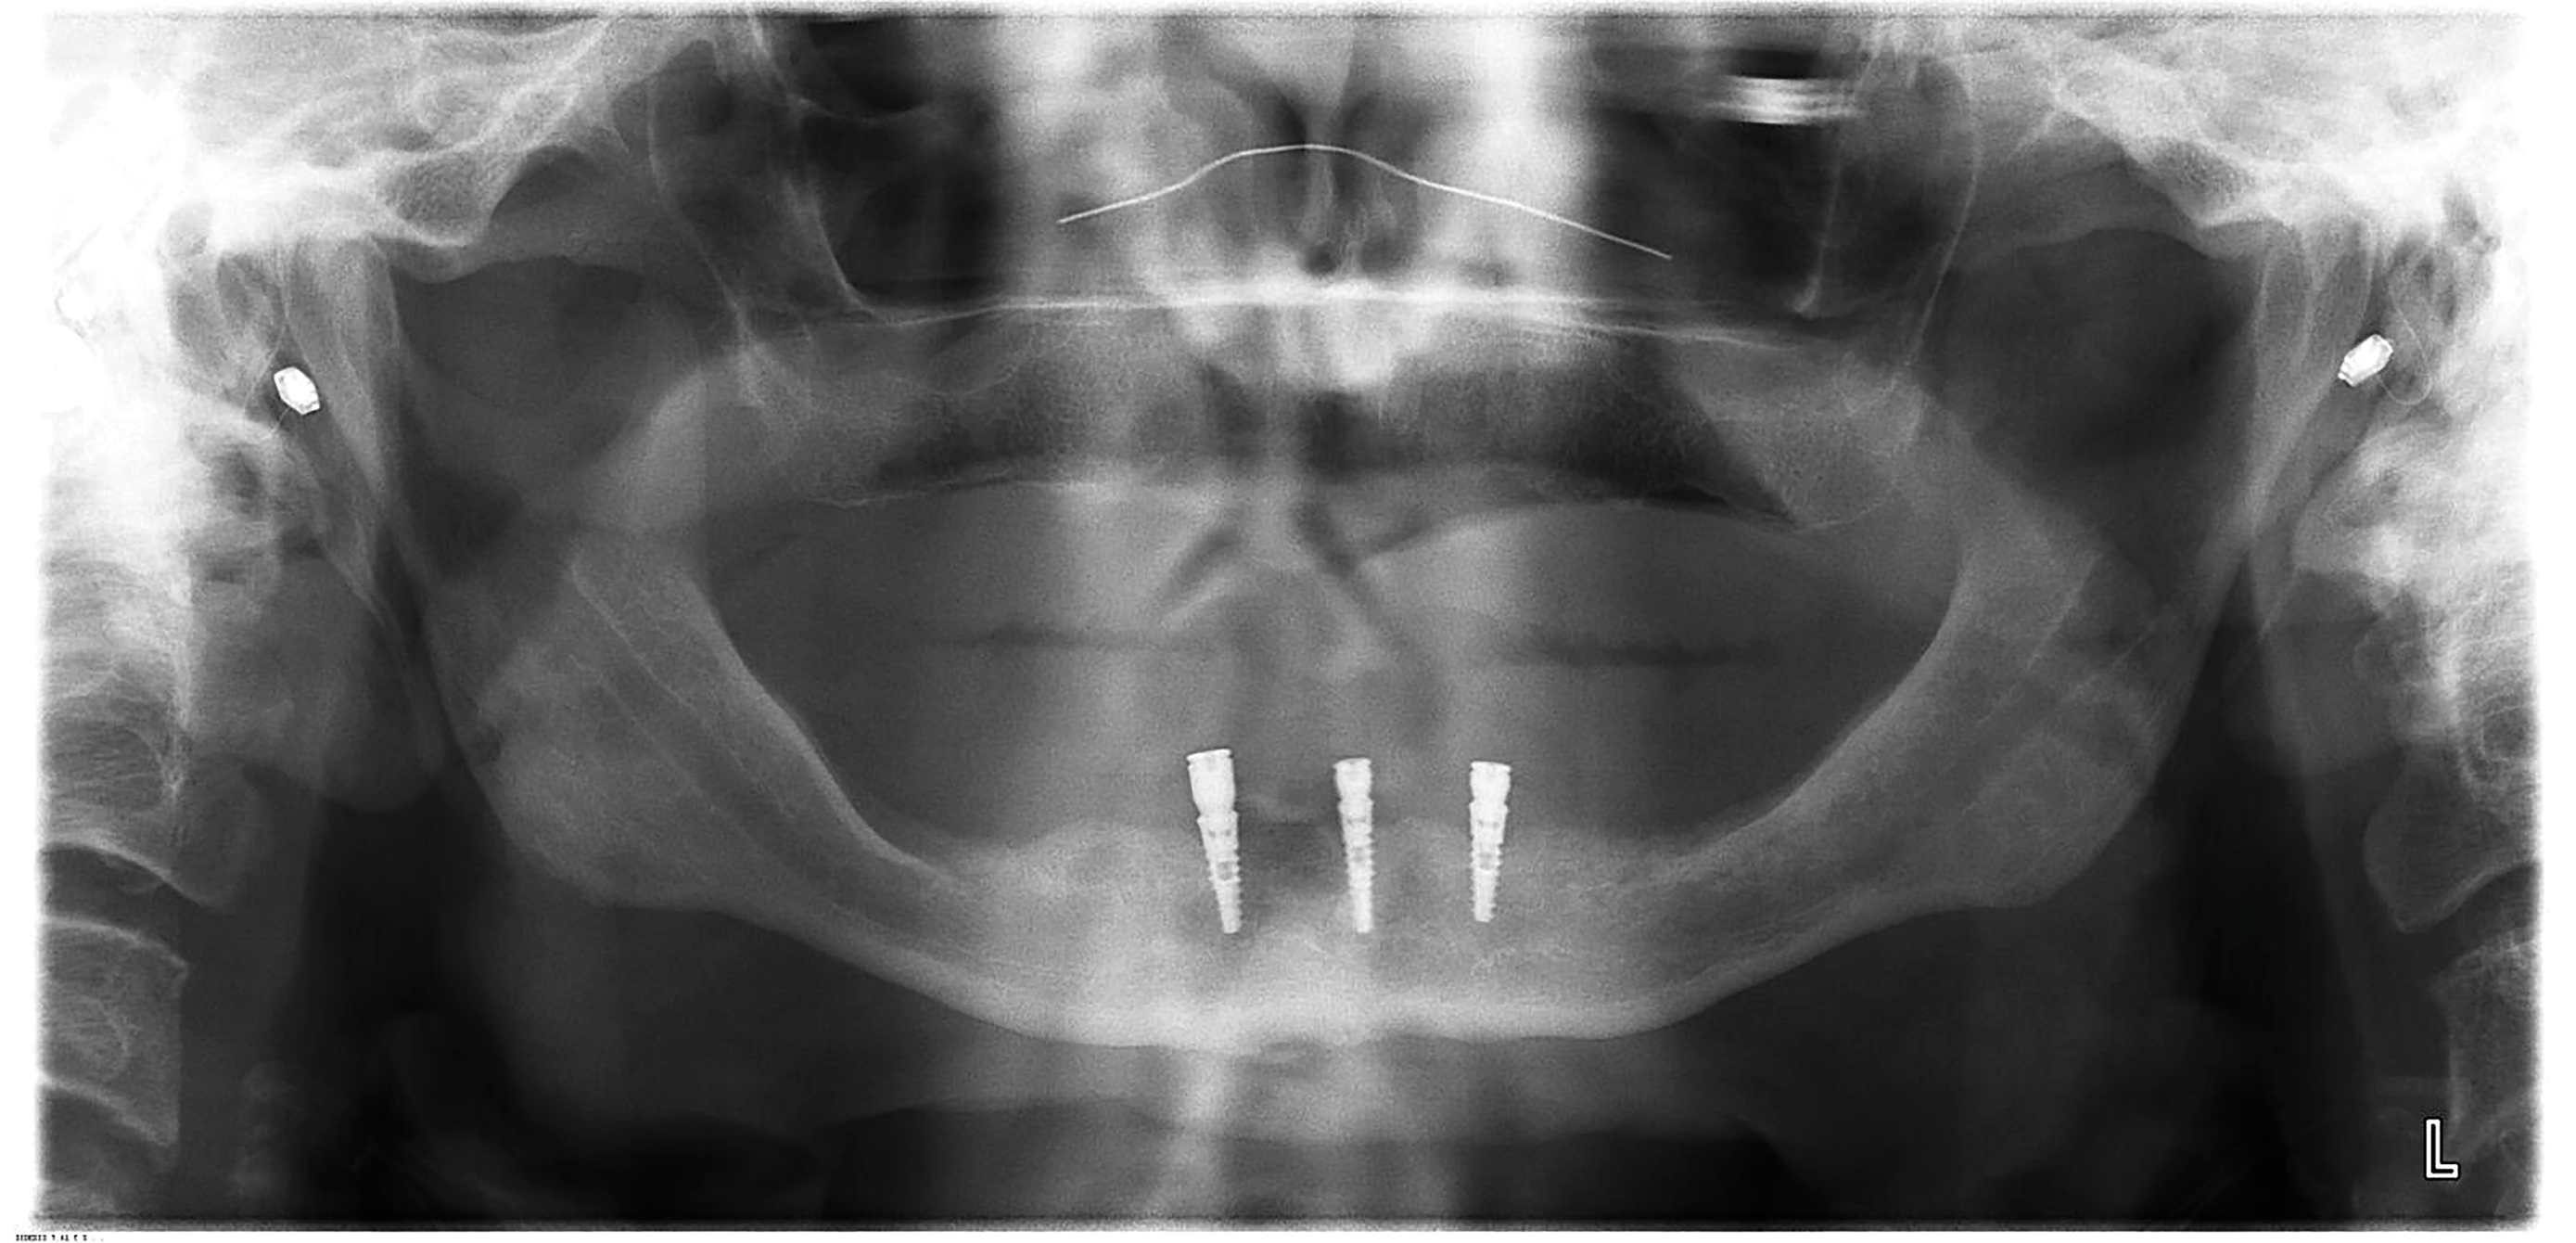

Six months after his last visit, the patient presented with complaints of unresolved pain in the lower gums and a referral from the denturist to assess the mandibular anterior region. The patient reported ongoing pain lasting more than 10 days without resolution despite repeated adjustments by the denturist to relieve areas of irritation. An area of ulceration was noted on the lingual gingiva of implant site No. 24, and a panoramic radiograph showed crestal peri-implant bone loss and thread exposure on all three implants (Figure 8), but this was unrelated to the observed lesion. Percussion of implant No. 24 and palpation of the buccal aspect did not yield a painful response. The tissue cuff surrounding the locator-type abutment was sensitive to palpation and localized to the lingual frenum adjacent to the implant.

Fig 7. Panoramic radiograph of implants following placement of locator-type attachments (3-month follow-up). Implants were well integrated with normal-appearing peri-implant bone.

Figure 7

Fig 8. Panoramic radiograph of implants at 6-month follow-up. Significant bone loss and thread exposure were noted around not only the affected implant No. 24 but all three implants.

Figure 8